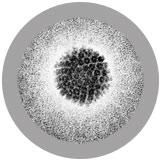

| Actual Size | This circular virus is about 2.75 micrometers, or 1/6500 the size of a dime! |